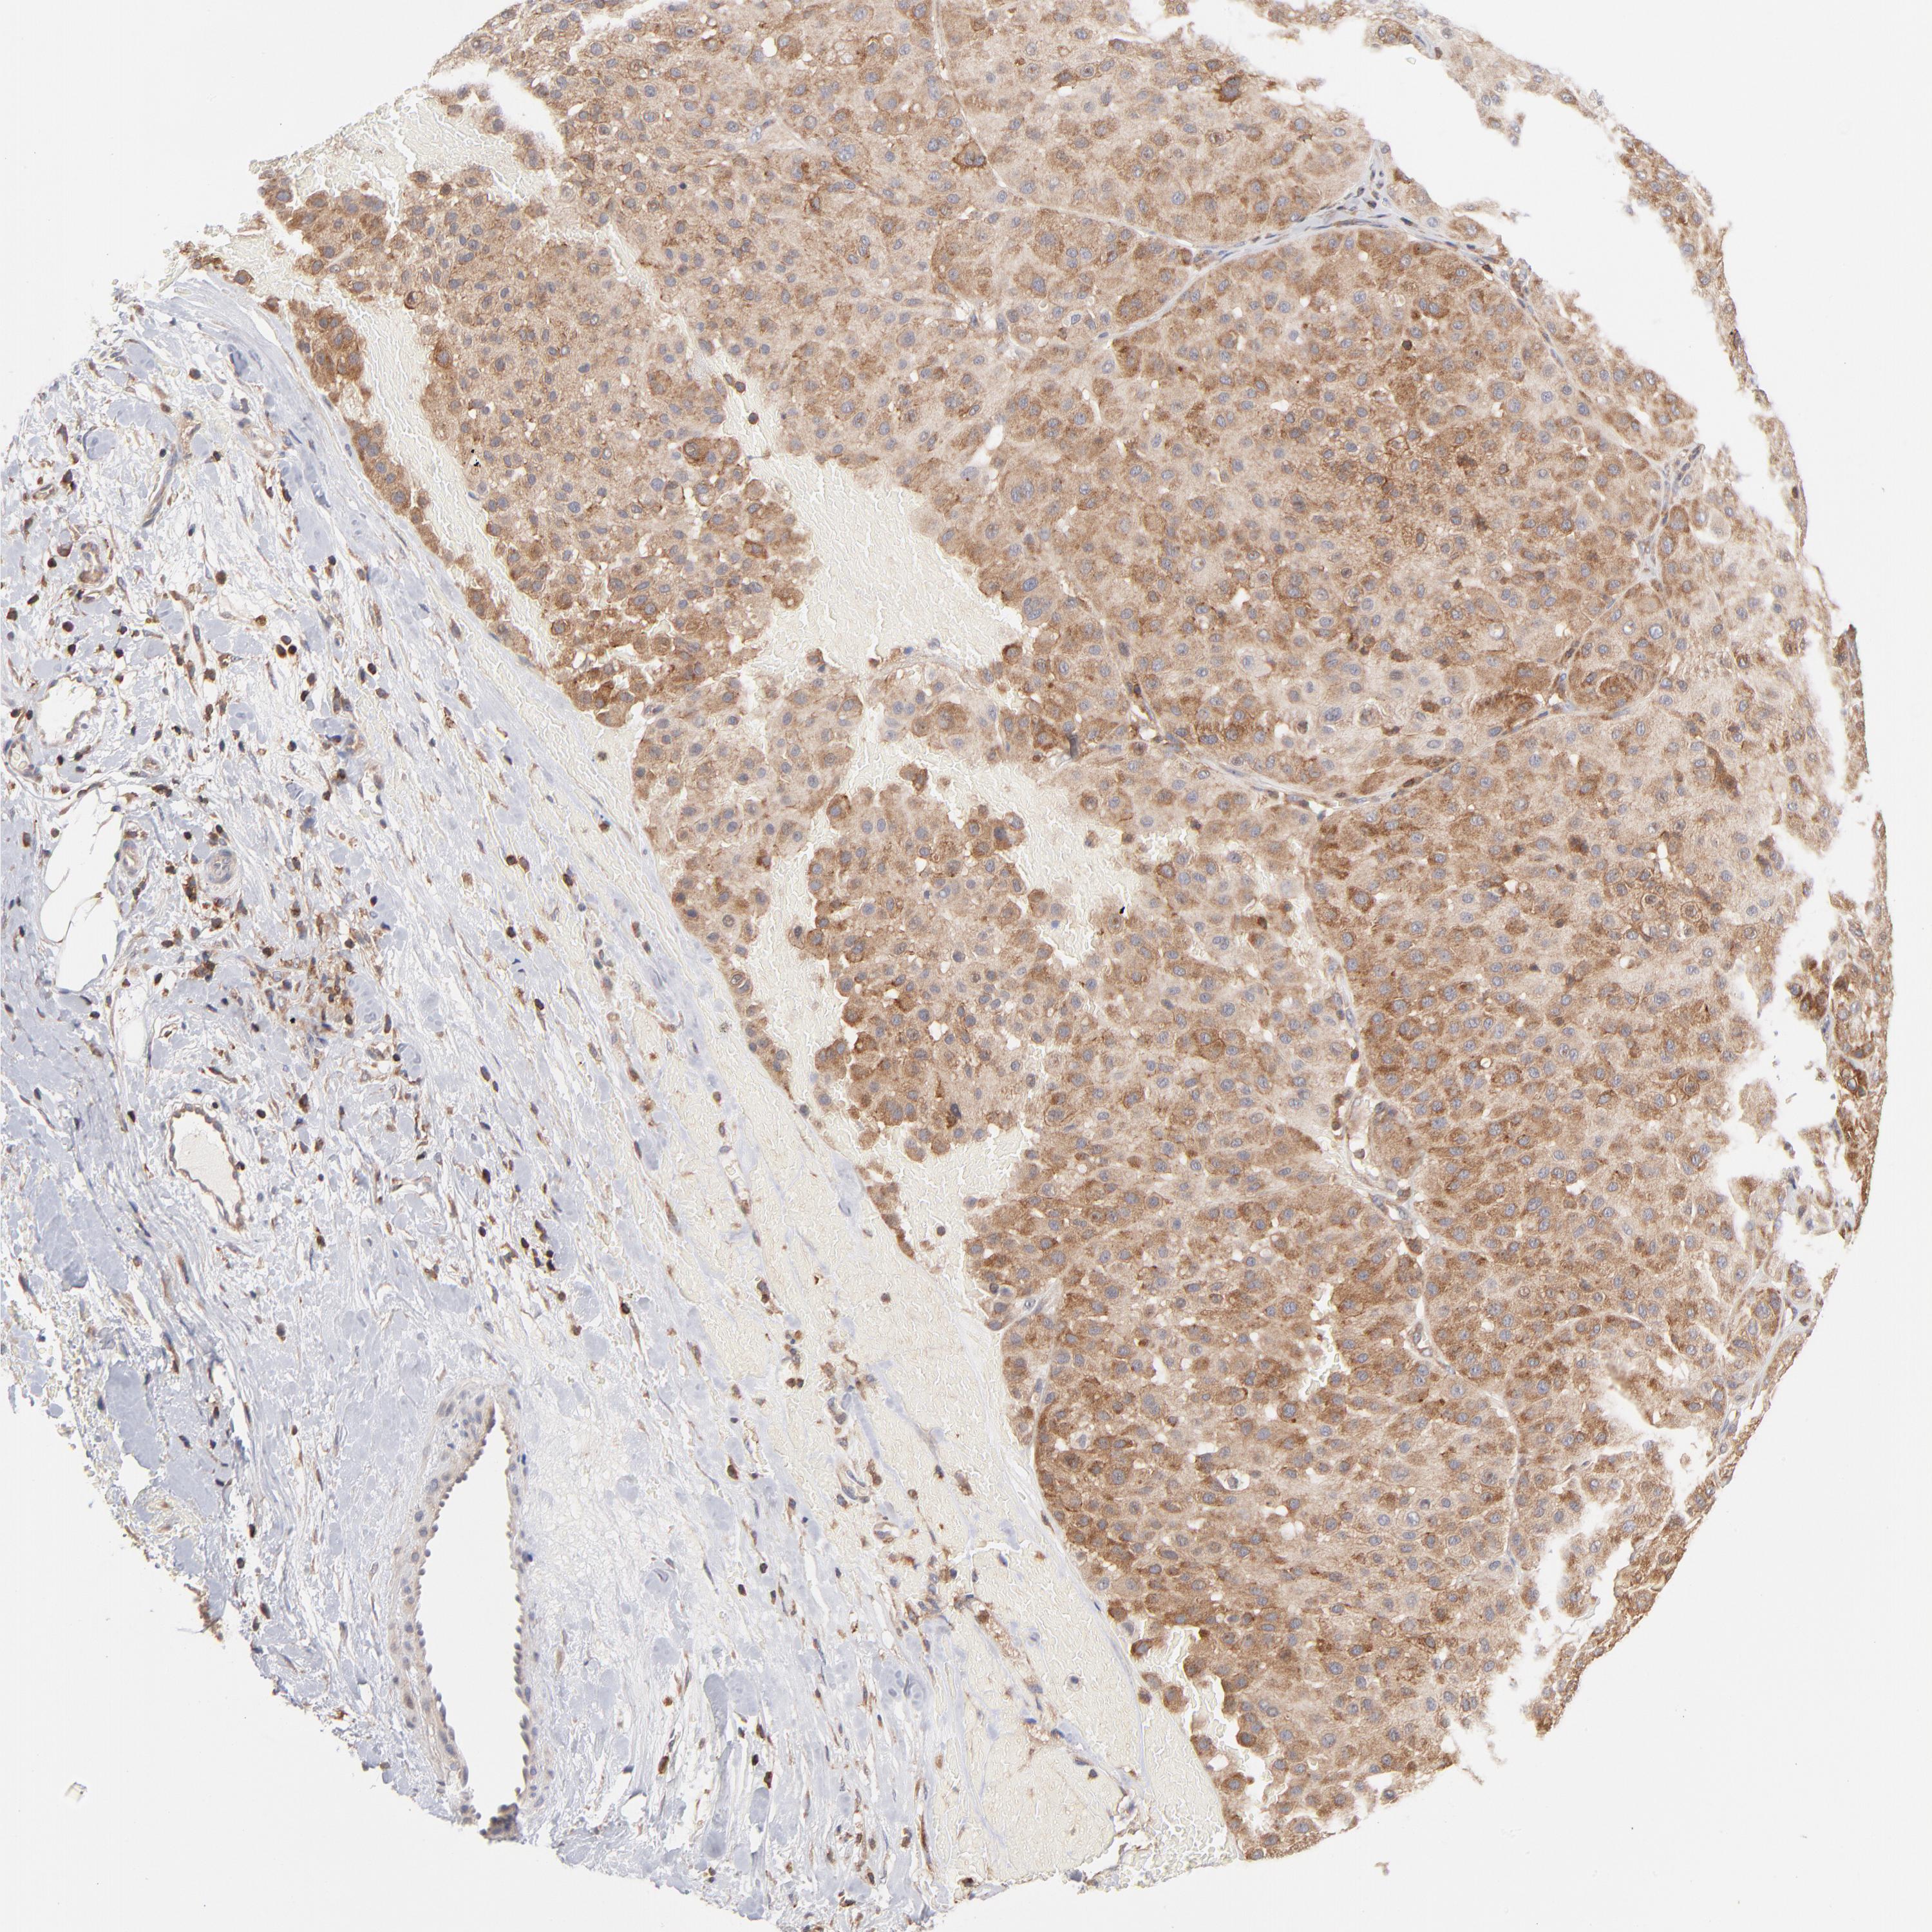

MELANOMA - Protein expressioni

A mouse-over function shows sample information and annotation data. Click on an image to view it in a full screen mode. Samples can be filtered based on level of antibody staining by selecting one or several of the following categories: high, medium, low and not detected. The assay and annotation is described here.

Note that samples used for immunohistochemistry by the Human Protein Atlas do not correspond to samples in the TCGA dataset.

Antibody stainingi

Antibody staining in the annotated cell types in the current human tissue is reported as not detected, low, medium, or high, based on conventional immunohistochemistry profiling in selected tissues. This score is based on the combination of the staining intensity and fraction of stained cells.

Each image is clickable and will lead to virtual microscopy that enables deeper exploration of all samples and also displays staining intensity scores, fraction scores and subcellular localization as well as patient and tissue information for each sample.

Antibody CAB009737

Staining

High

Medium

Low

Not detected

Intensity

Strong

Moderate

Weak

Negative

Quantity

>75%

75%-25%

<25%

None

Location

Nuclear

Cytoplasmic/membranous

Cytoplasmic/membranous,nuclear

Malignant melanoma, Metastatic site